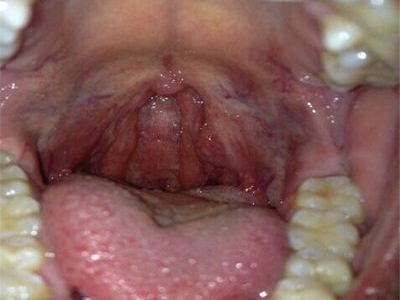

扁桃体癌属于扁桃体恶性肿瘤,为口咽部常见恶性肿瘤之一,病因可能与烟、酒等因素有关。本病可引起咽部不适、异物感、疼痛感、溃烂、出血等症状,临床常通过活检进行确诊,临床多采取手术切除治疗。

扁桃体癌通常先表现为咽部不适、异物感,随后咽痛加剧,可出现吞咽困难。同时,检查可见扁桃体肿大,表面溃烂,呈结节状隆起,易出血,可与周围组织粘连。

扁桃体癌通常可采取扁桃体切除术进行治疗,伴有颈部淋巴结转移者同时行颈清扫术,术后辅以放疗及化疗等措施。